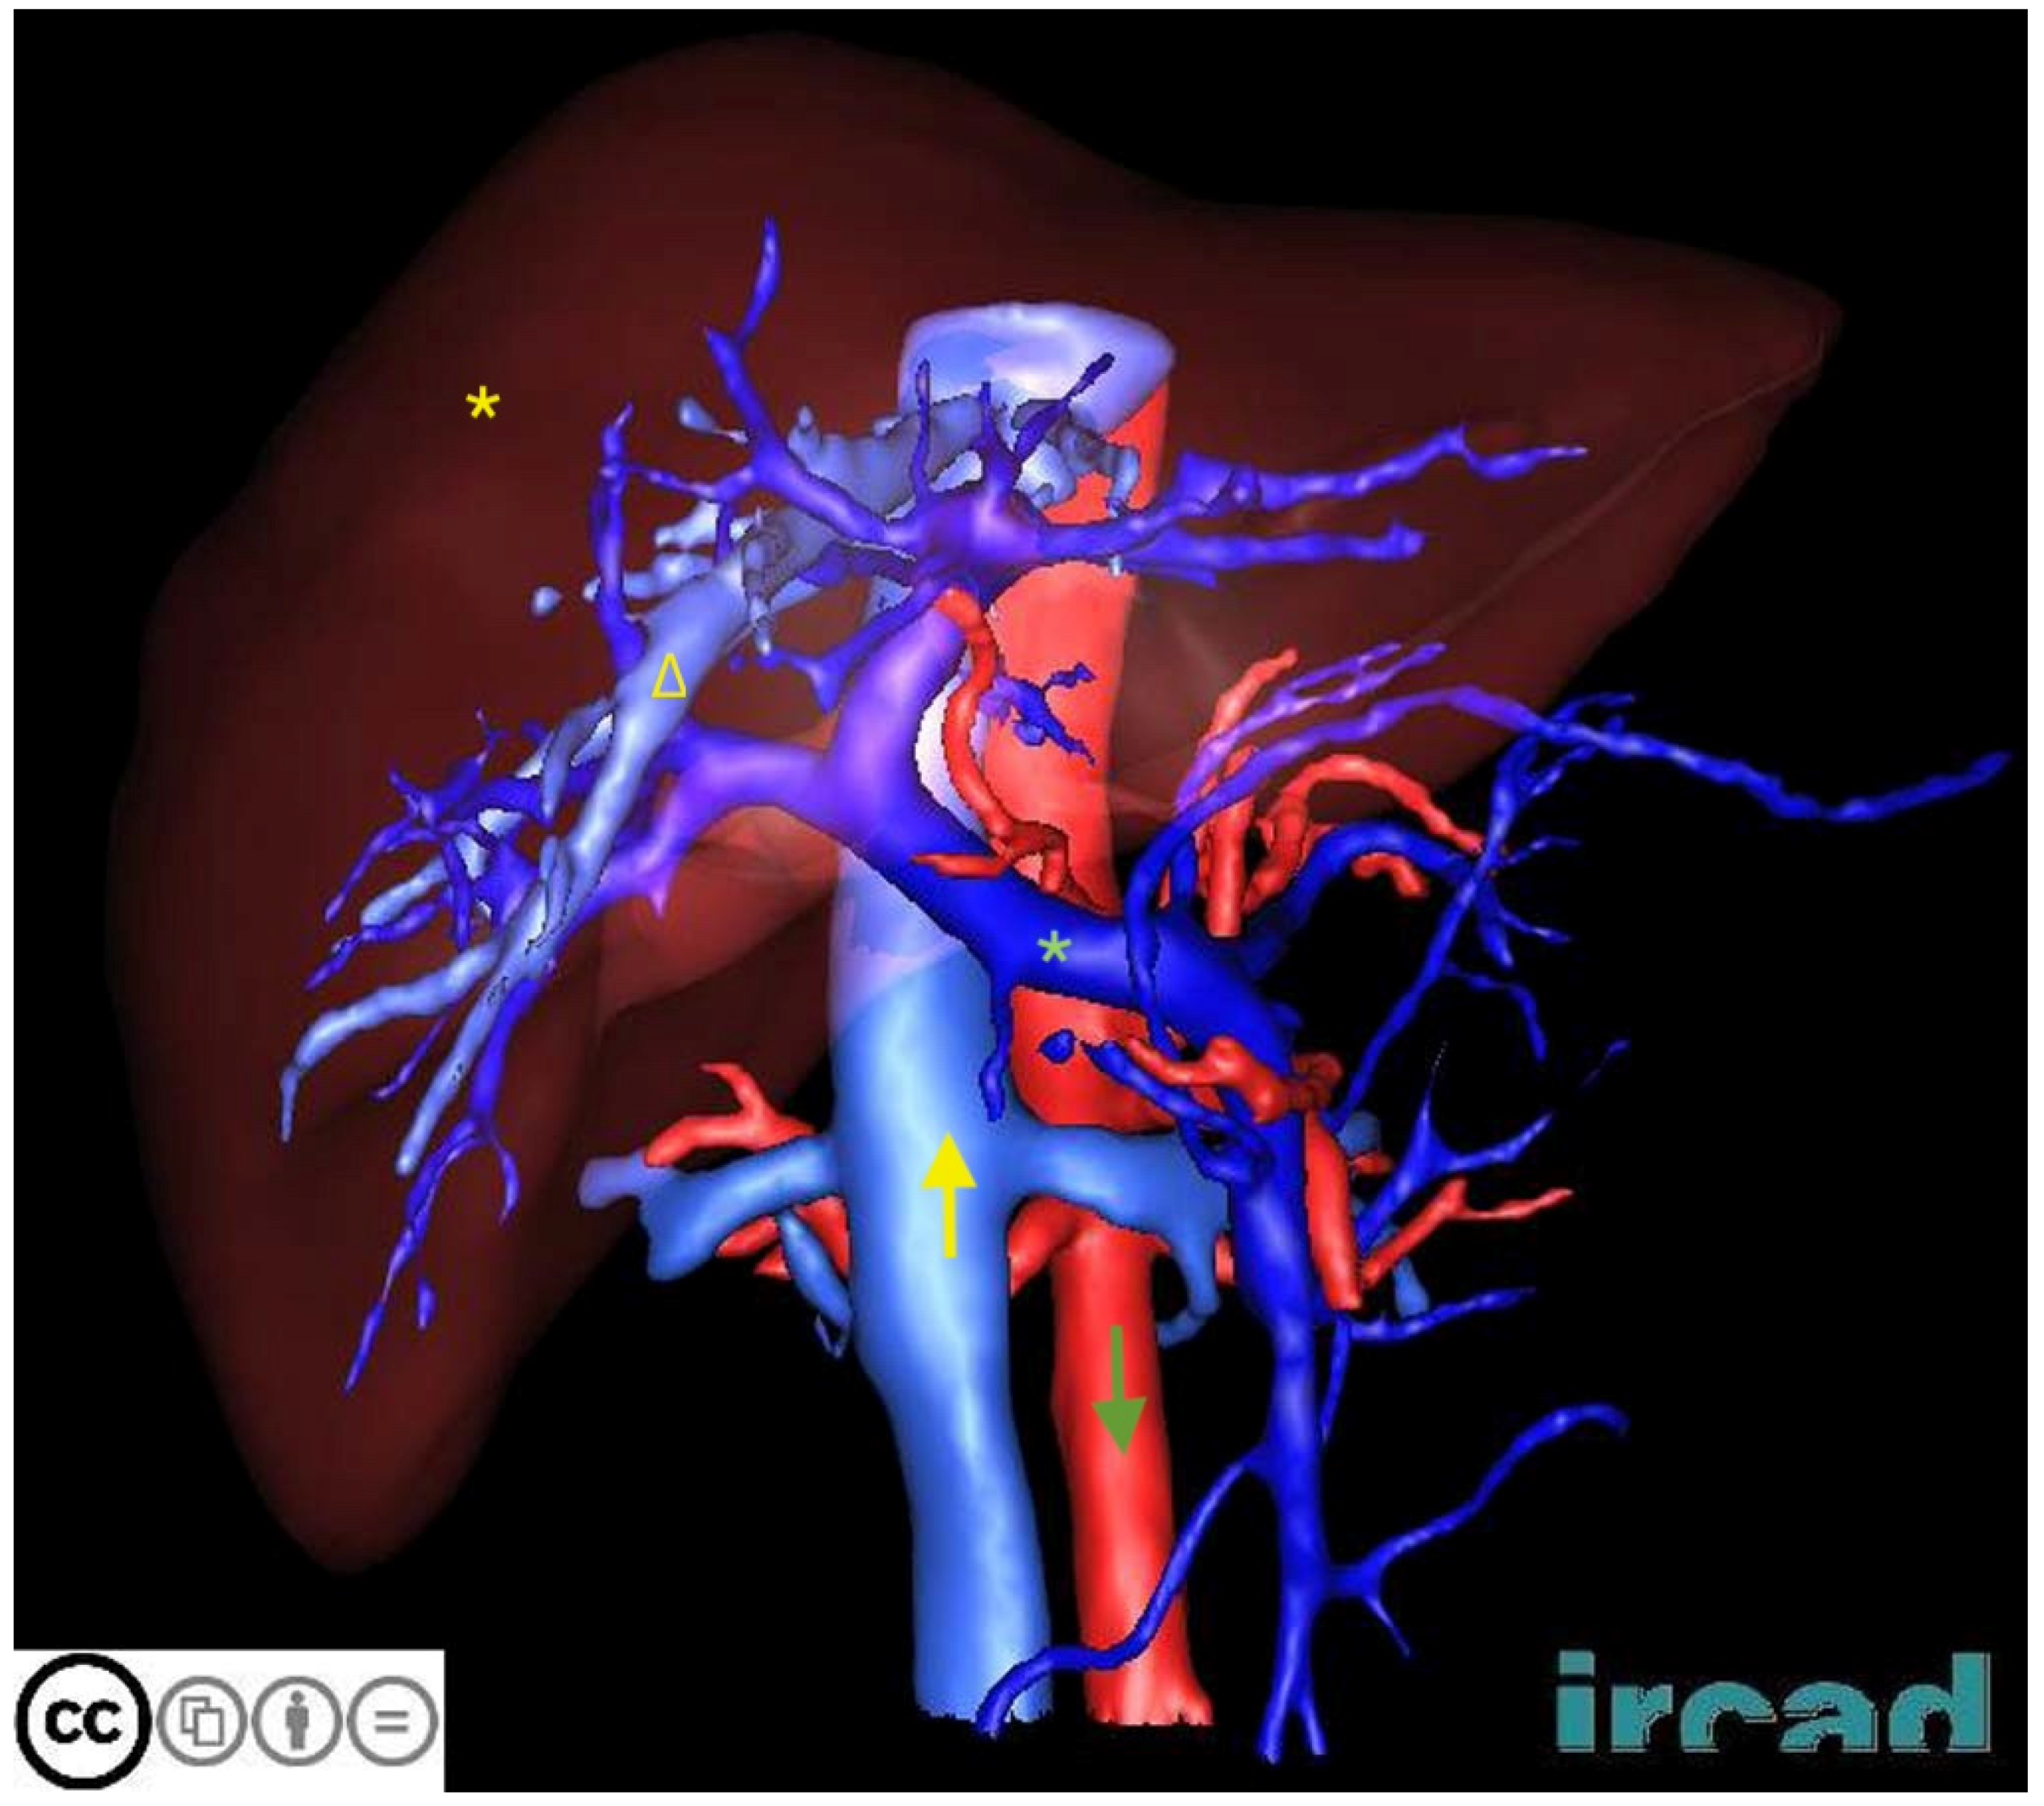

| 3DIRCADb | CT scans from 20 patients with annotations for liver and liver tumor segmentation | Detailed 3D reconstruction data aid the development of segmentation algorithms for complex liver structures | Small sample with limited case types |

- Soler, L.; Hostettler, A.; Agnus, V.; Charnoz, A.; Fasquel, J.; Moreau, J.; Osswald, A.; Bouhadjar, M.; Marescaux, J. 3D Image Reconstruction for Comparison of Algorithm Database: A Patient Specific Anatomical and Medical Image Database; Technical Report; IRCAD: Strasbourg, France, 2010. [Google Scholar]